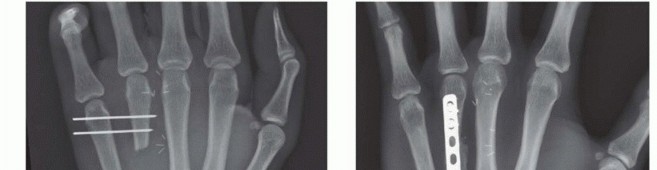

TECH FIG 4 • A-C. Patient with torsional injury to long and ring fingers leading to spiral fractures of the third and fourth metacarpals. The combined injury made it possible for malrotation to develop. D.

TECH FIG 4 • (continued) G,H. Motion at 6 weeks after surgery. The periosteum is elevated at the fracture site to assist with assessment of fracture reduction. As much of the interosseous muscle is left attached to the metacarpal as feasible to preserve blood supply to the bone.The fracture is reduced and provisionally stabilized with reduction clamps (TECH FIG 4D).

LAG SCREW FIXATION

Long oblique and spiral fractures whose lengths are at least twice the diameter of the bone at the level of the fracture are amenable to limited fixation with screws only (see TECH FIG 4A-C).Appropriately sized lag screws (1.4 to 2.7 mm) are placed. Typically, two or three screws are used (TECH FIG 4E,F).The first screw is placed perpendicular to the fracture in order to compress it and the second screw is placed perpendicular to the bone to resist longitudinal forces.In order to get proper compression with a lag screw construct, it is important to overdrill the near cortex.When using a 2.0-mm screw system, a 1.5-mm drill bit is used to drill both cortices. The near cortex is then overdrilled with a 2-mm drill bit.A countersink is used to maximize contact between the head of the screw and the bone. The size of the screw is measured and an appropriately sized screw is placed.The periosteum and interosseous muscle fascia are reapproximated to cover the screws. The juncturae tendinum are repaired and the skin is closed in standard fashion.The hand is then immobilized with the MP joints flexed 70 to 90 degrees with a forearm-based splint. Early motion can be started as early as 4 to 7 days, depending on fracture stability (TECH FIG 4G,H).